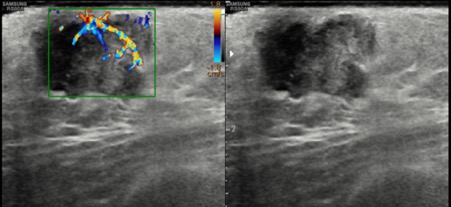

Bilateral Digital mammography , Craniocaudal (CC) and Mediolateral oblique (MLO) view revealed an irregular , high density mass with indistinct margin in retroareolar region with retracted nipple. No microcalcifications was seen. No significant axillary lymph nodes were present. Ultrasound of left breast showed an irregular, heterogeneously hypoechoic mass with indistinct margin and mild posterior acoustic enhancement, measuring about 2.5x1.9x1.3cm in retroareolar region. Internal vascularity was increased on colour doppler. On strain sonoelastogram, the mass showed increased stiffness suggestive of hard consistency. The imaging features are highly suspicious for male breast cancer and thus the mass was classified as BIRADS category 5 lesion and Ultrasound guided biopsy was advised. Patient underwent left modified radical mastectomy and final histopathological report was Invasive Lobular carcinoma. No nipple or lymphovascular invasion was identified.

The imaging features are highly suggestive of male breast cancer and thus the mass was classified as BIRADS category 5